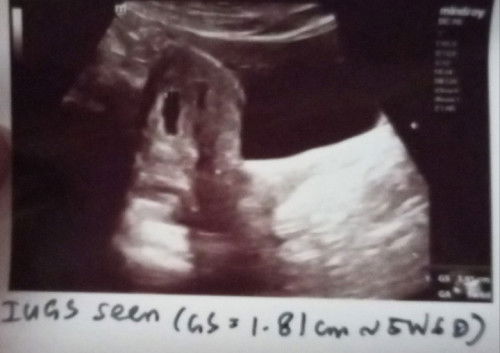

Ultrasound scan at 5w6d.

First ultrasound scan at 5w6d. Normal ke kalau gestational sac bentuk macam tu and tak nampak yolk sac and fetal pole lagi? Saya try Google tapi tak dapat jawapan yang tepat sebab saya curious. Tak terlintas nak tanya Dr. Cuma Dr kata nampak macam kantung kosong lagi tapi 2 minggu boleh datang scan balik, sekarang ni maybe agak awal lagi katanya untuk nampak. Update : Baru text klinik yang pergi buat scan and Dr kata bentuk kantung sedikit irregular, and dalam 2 minggu kena datang untuk scan balik untuk pastikan kandungan berkembang atau tak. Kalau ada bleeding atau sakit perut, boleh datang scan terus. Taktahu nak rasa apa, huhu. Nervous, nak nangis. But kena kuat kan, semoga Allah jaga kandungan saya ini. Cuz I'm pretty hopeful about it. 🤲🏻